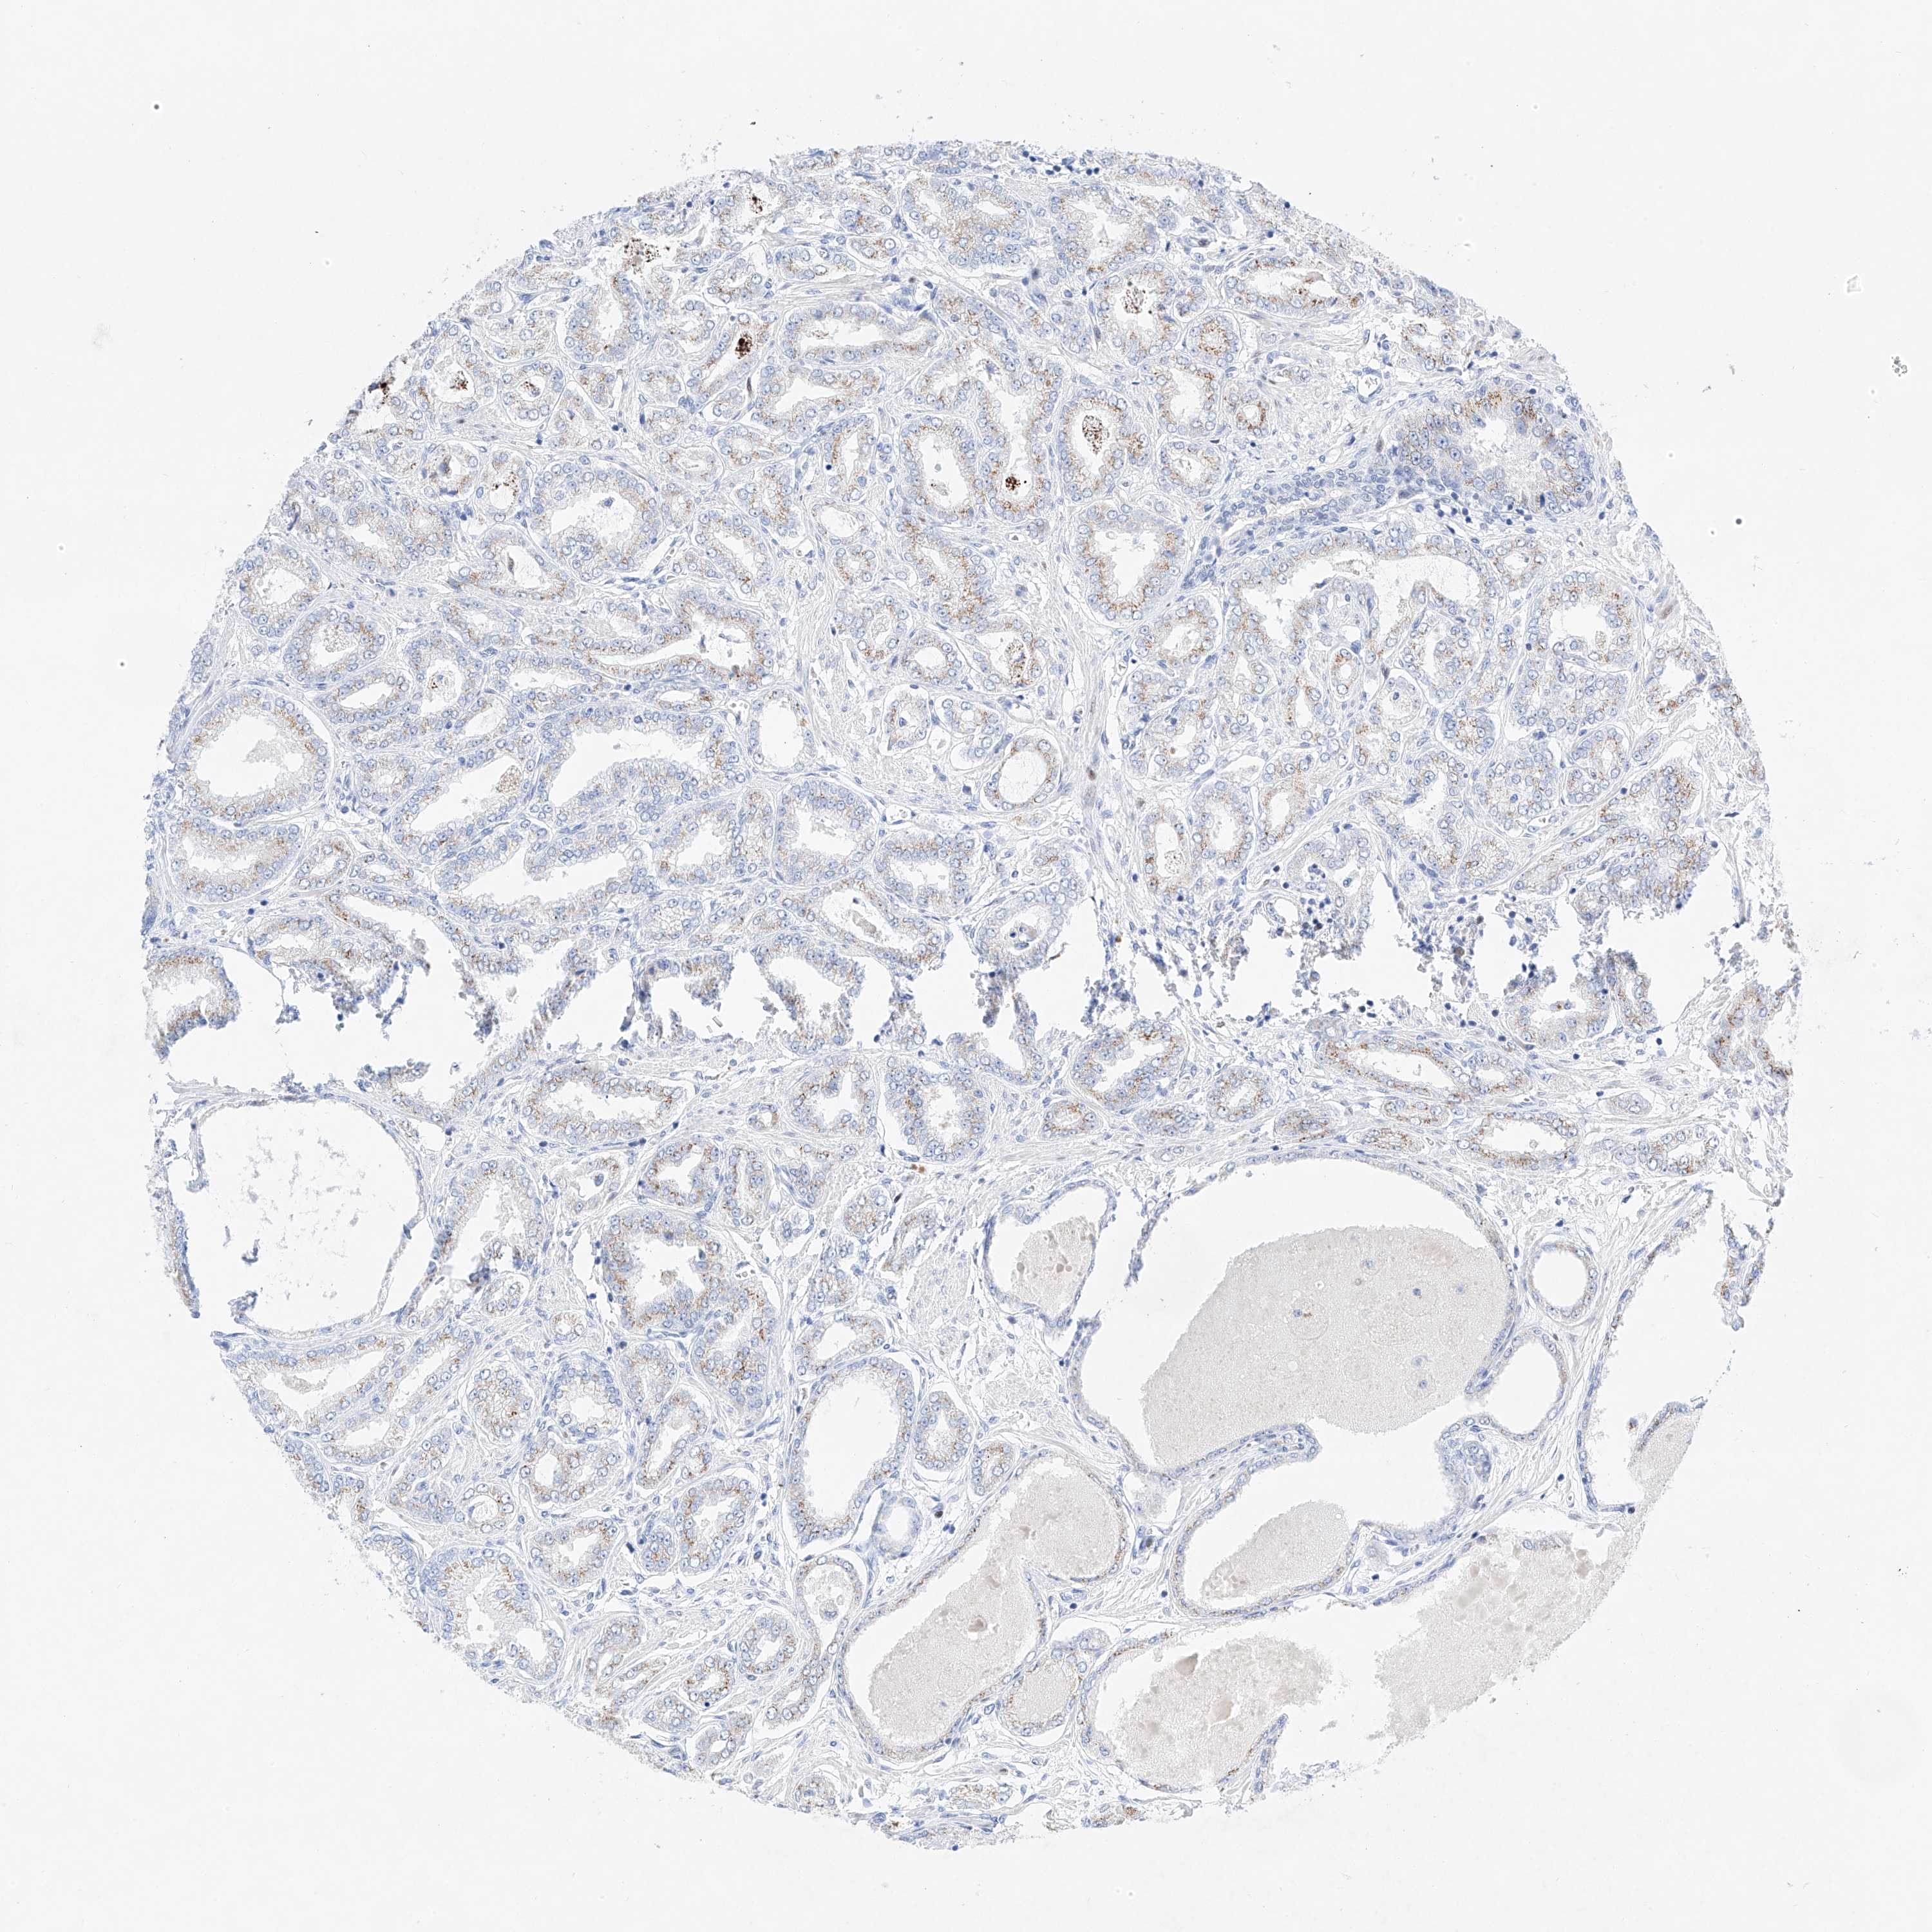

NT5C3B